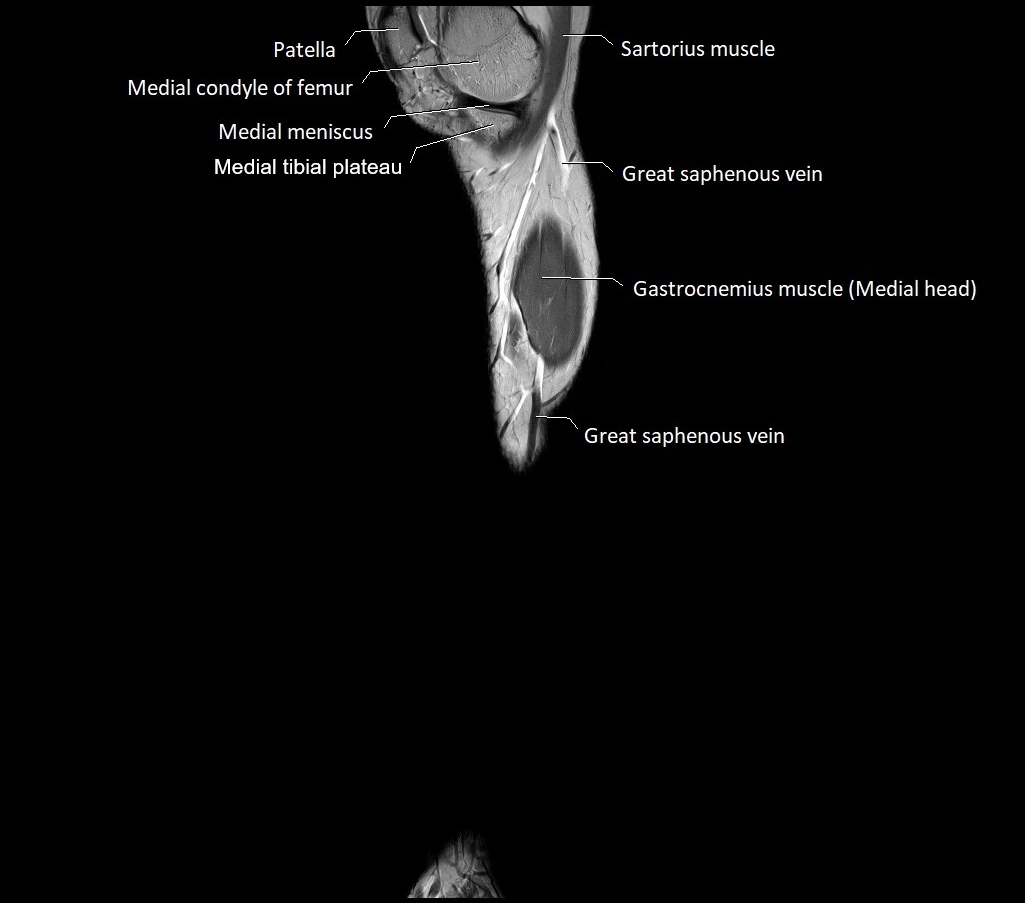

MRI image